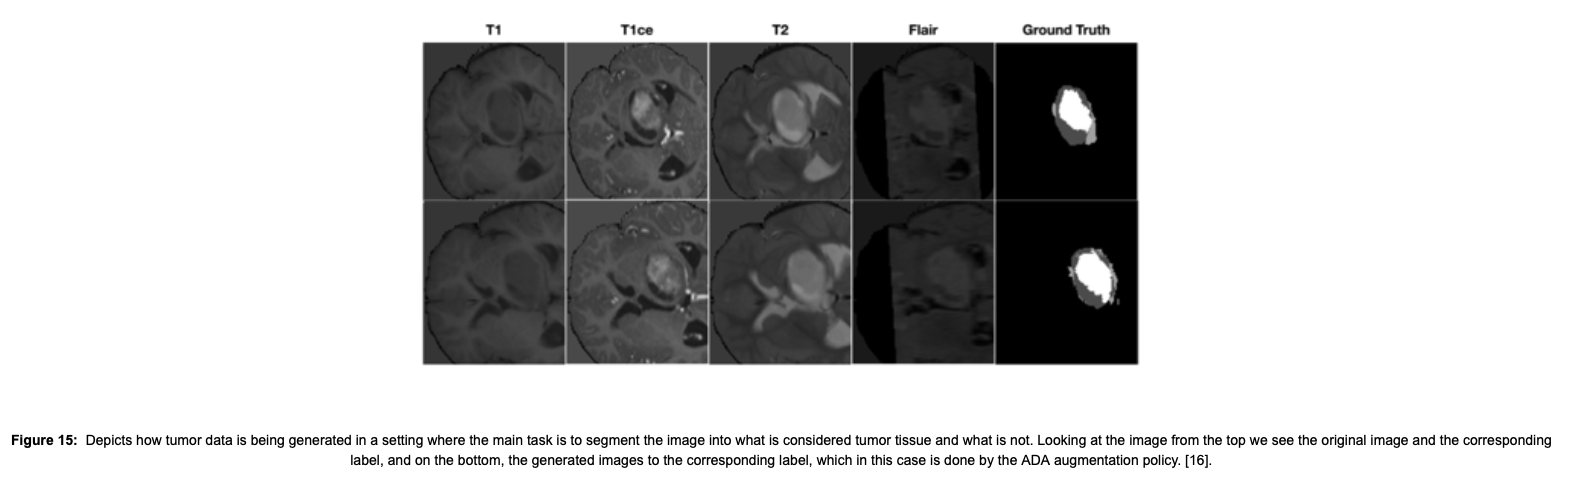

This last subsection is only meant for completion purposes, as the research topic at hand is whether image synthesis can be applied to few-shot medical settings. In the current status quo, top-performing GANs are capable of generating realistic-looking medical images by FID (explained below in section 3) standards that can fool trained experts in a visual Turing test and comply with some metrics. However, segmentation results suggest that no GAN is capable of reproducing the full richness of medical datasets. The two figures below show some medical use cases.

[16] Xu, J., Li, M., & Zhu, Z. (2020). Adaptive Data Augmentation for 3D Medical Image Segmentation. arXiv. https://doi.org/10.48550/ARXIV.2010.11695